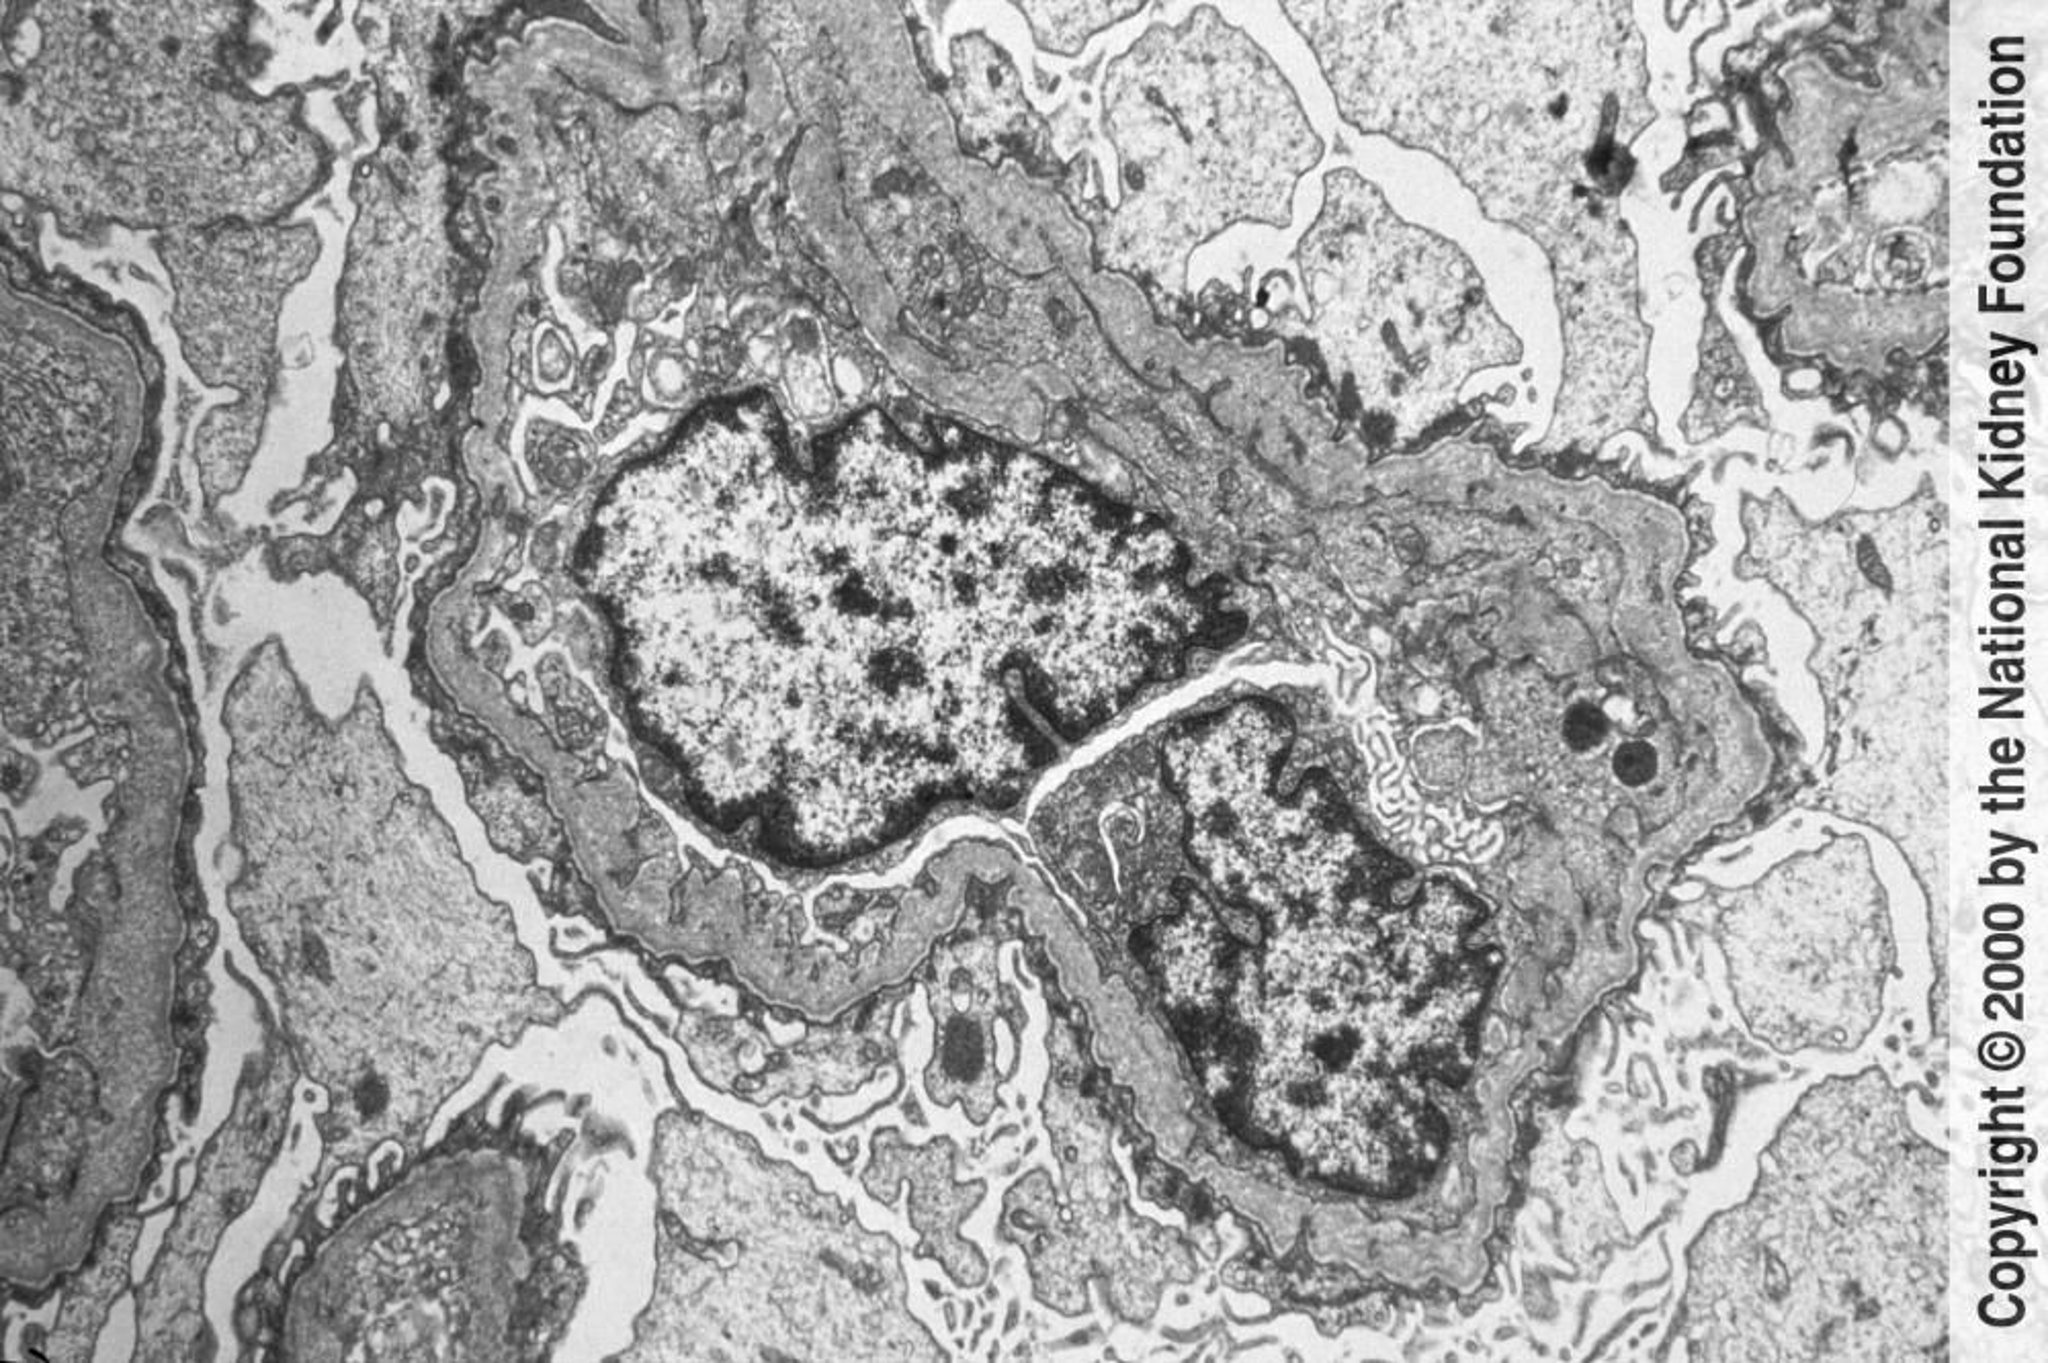

Síndrome de Alport (nefritis hereditaria)

Las membranas basales glomerulares muestran adelgazamientos y engrosamientos irregulares con un aspecto laminado en cesta de mimbre bajo microscopia electrónica de transmisión. Los cambios son causados por la lesión y el remodelado (×6000).

Image provided by Agnes Fogo, MD, and the American Journal of Kidney Diseases' Atlas of Renal Pathology (véase www.ajkd.org).